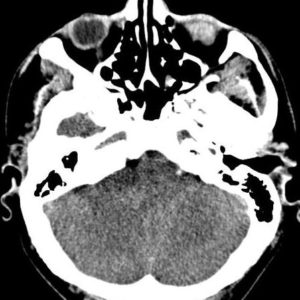

U dây VIII

Lượt xem: 132» 24-11-2018 -

U dây VIII

Lượt xem: 130» 24-11-2018 -

U dây VIII

Lượt xem: 153» 24-11-2018 -

U dây VIII

Lượt xem: 147» 24-11-2018 -

U dây VIII

Lượt xem: 117» 24-11-2018 -

U dây VIII

Lượt xem: 149» 24-11-2018 -

U dây VIII

Lượt xem: 143» 24-11-2018 -

U dây VIII

Lượt xem: 158» 24-11-2018